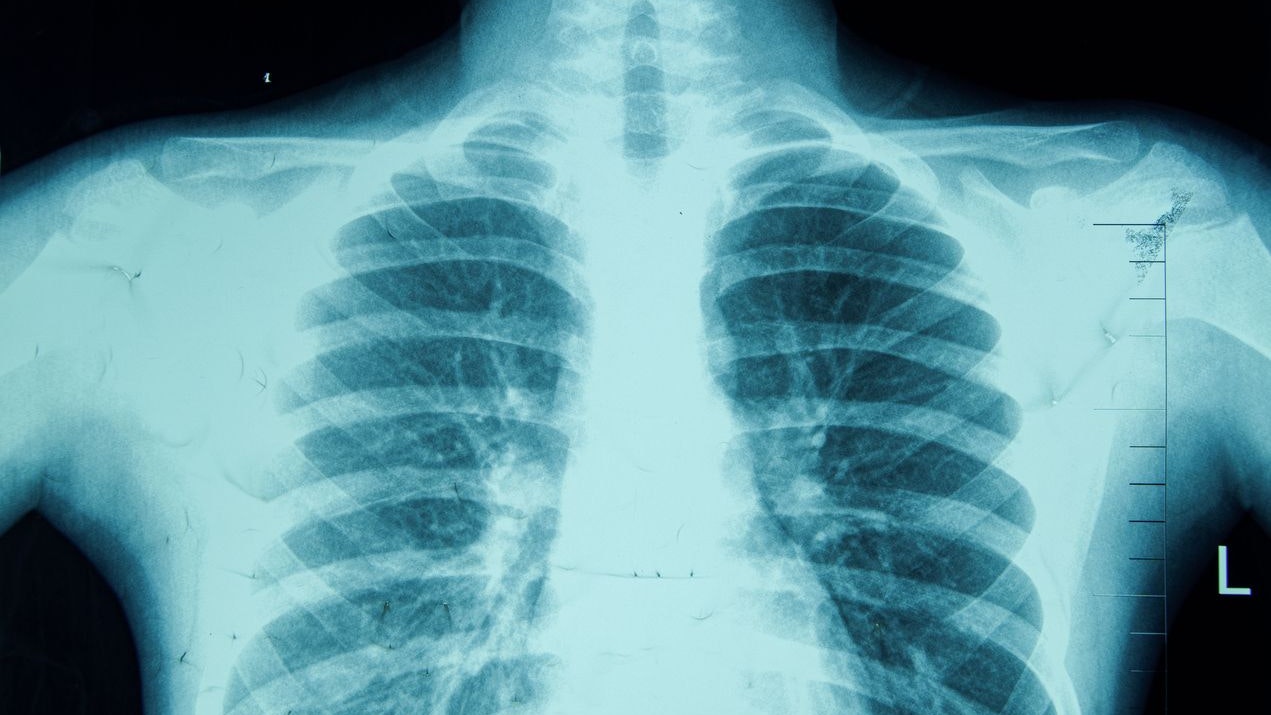

Lungenkrebs wird meist erst in einem schwer behandelbaren Spätstadium entdeckt.